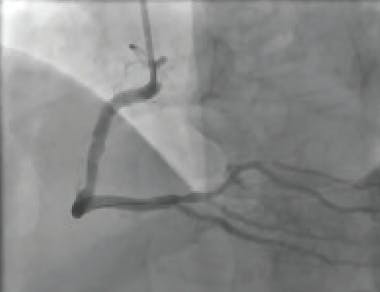

INTERVENTION

A radial approach was used for intervention. The diagnostic catheter revealed a totally occluded RCA with acute stent thrombosis and TIMI 0 flow (Figure 1). Using a whisper wire, the lesion was crossed. Two runs were then performed using CAT RX, which resulted in establishment of flow (Figure 2 and Figure 3). Subsequently, balloon dilatation was performed in the stent with a 2.5- X 20-mm compliant balloon; a 3.5- X 38-mm Resolute Onyx™ stent (Medtronic) was deployed in the mid-RCA distal to the original stent and was postdilated with a 4- X 15-mm noncompliant balloon. TIMI 3 flow was noted postprocedure, with grade 3 myocardial blush (Figure 4).

Figure 1. The occluded RCA with acute stent thrombosis.

Figure 2. Intraprocedural angiogram with CAT RX (white arrow).

Figure 3. Angiogram following aspiration with CAT RX.